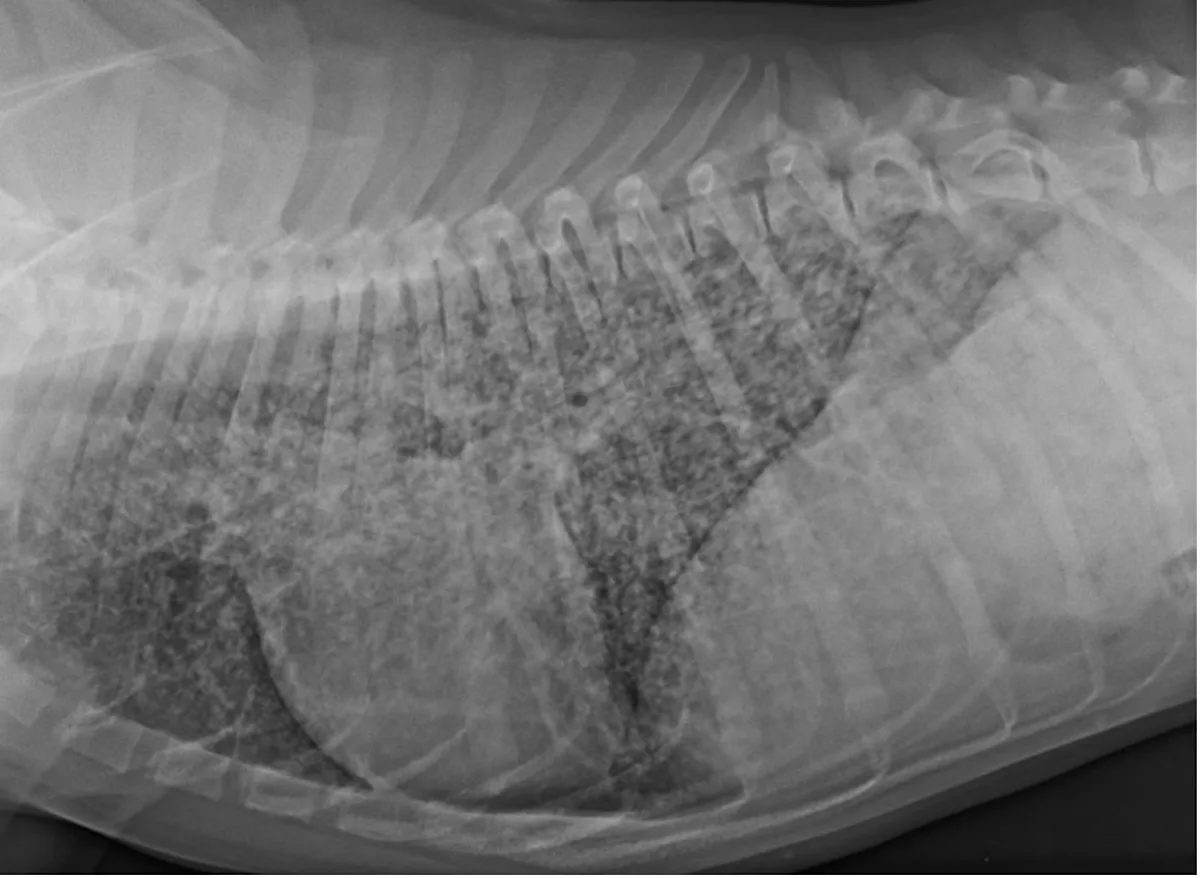

Pulmonary changes may include enlarged hilar lymph nodes, alveolar pattern, and either large solitary masses or a diffuse miliary pattern (Figure 2).19 Definitive diagnosis can be made via serum or, preferably, urine evaluated via Blastomyces spp quantitative antigen test.20,21 Biopsy can be performed if suspicion remains despite a negative result. Culture is not routinely performed, as Blastomyces spp culture requires an enhanced biocontainment unavailable in routine diagnostic laboratories.

Lateral thoracic radiograph with a diffuse miliary pattern from a 7-month-old, intact male cane corso with a swollen right pelvic second digit, enlarged popliteal lymph node, coughing, and tachypnea